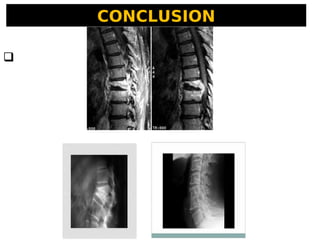

CONCLUSION

 Le MAL DE POTT est une affection invalidante.

 Son diagnostic doit être le plus précoce

possible au mieux basé sur une preuve

bactériologique ou histologique.

 La précocité du traitement anti bacillaire est le

seul garant d’une guérison sans séquelle car les

complications neurologiques font toute la gravité

de la maladie.